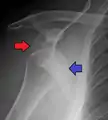

| Anterior dislocation of the left shoulder. | |

In over 95% of shoulder dislocations, the humerus is displaced anteriorly.[7] In most of those, the head of the humerus comes to rest under the coracoid process, referred to as sub-coracoid dislocation. Sub-glenoid, subclavicular, and, very rarely, intrathoracic or retroperitoneal dislocations may also occur.[8]

Anterior dislocations are usually caused by a direct blow to, or fall on, an outstretched arm. The person typically holds his/her arm externally rotated and slightly abducted.

A Hill–Sachs lesion is an impaction of the head of the humerus left by the glenoid rim during dislocation.[6] Hill-Sachs deformities occur in 35–40% of anterior dislocations. They can be seen on a front-facing X-ray when the arm is in internal rotation.[9] Bankart lesions are disruptions of the glenoid labrum with or without an avulsion of bone fragment.

An anterior dislocation of the shoulder